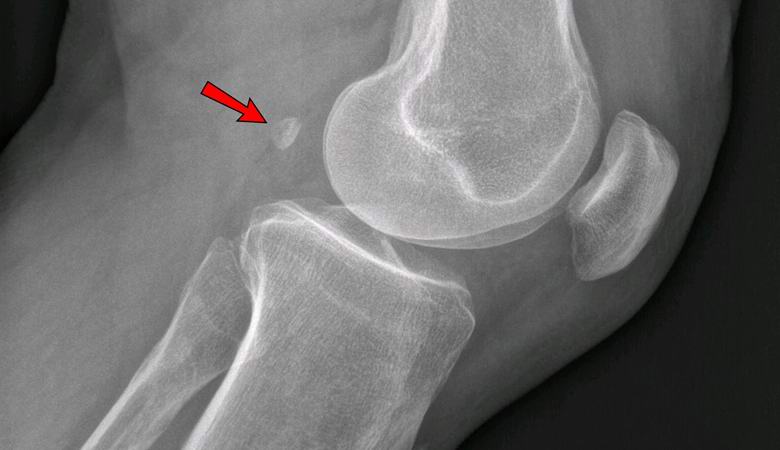

Ha 1918-ban a földművelőknek mindössze 11% -ánál volt fabella legalább egyben láb, ma az emberek 39% -ában fordul elő. Ez a szezám alakú a csont az ín vastagságában növekszik a térd mögött és anatómiailag hasonlít mikroszkopikus patella-ra.

Az orvosok még mindig nem tudják meghatározni, hogy miért van ez az alapvetés visszatér az emberi testbe, és miért van rá szükség. első az orvosok szerint a Fabella csak ártalmatlan, felesleges szerv, a szakértők azonban már arra a következtetésre jutottak, hogy a térdben van jelen osteoarthritist okozhat. Még orvosok is voltak aki mindenkinek, akinek fabella van, javasolta annak eltávolítását sebészi úton, hogy az időskorban ne szenvedjen a deformációtól osteoarthritis.

Ma minden biológiai tankönyv jelzi, hogy az emberi csontváz 206 csontból áll. A jövőben azonban talán ilyen adatok elavultnak tekintik, és ott 206-208 csontról fognak beszélni, mivel sok embernek már van egy vagy mindkét meséje. ezt egy csontot, amelyet sok orvos szerint, függeléknek nevezhetünk csontváz “, mert nem csak haszontalan, hanem szolgálhat egészségügyi problémákat okozhat. Érintkezve a térd porcával, súlyos osteoarthritishez vezet.